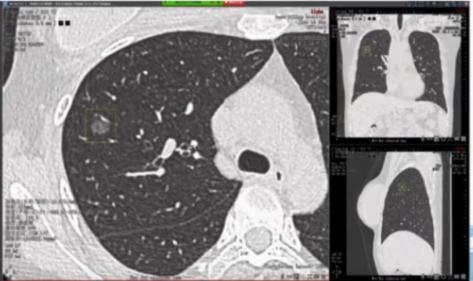

患者,女,49岁,既往无吸烟史;CT发现双肺小结节1年,为进一步明确诊断进行薄层CT扫描并将影像学资料交与AI进行进一步判定。

AI判读发现患者右上肺有10.8*8.5 mm结节,且在左肺见7.2*5.3 mm结节。两结节均呈现空泡征且有新生血管生成,左肺结节更是存在分叶征。

最初发现右肺结节时,由于结节较小判读比较困难,医生并没有给出明确诊断而时嘱托患者继续随访。本次患者影像学经AI评估,认为患者右上肺结节可能高度恶性可疑,左下肺结节恶性风险稍低但依然存在。

由于患者存在双侧肺结节且恶性可能性大,尽管手术以及术后管理存在风险,但经过胸外科和呼吸内科MDT评估后,该患者接受同时的双侧肺结节切除。

术中病理提示:患者右肺结节为浸润性肺腺癌,左肺结节为微浸润性腺癌,术后病理与术中冰冻病理一致。